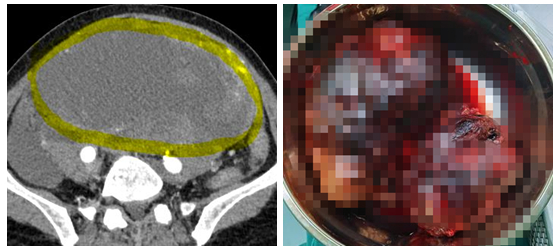

半年前家住桃源县的李阿姨发现自己出现不明原因上腹部饱胀、食欲减退...